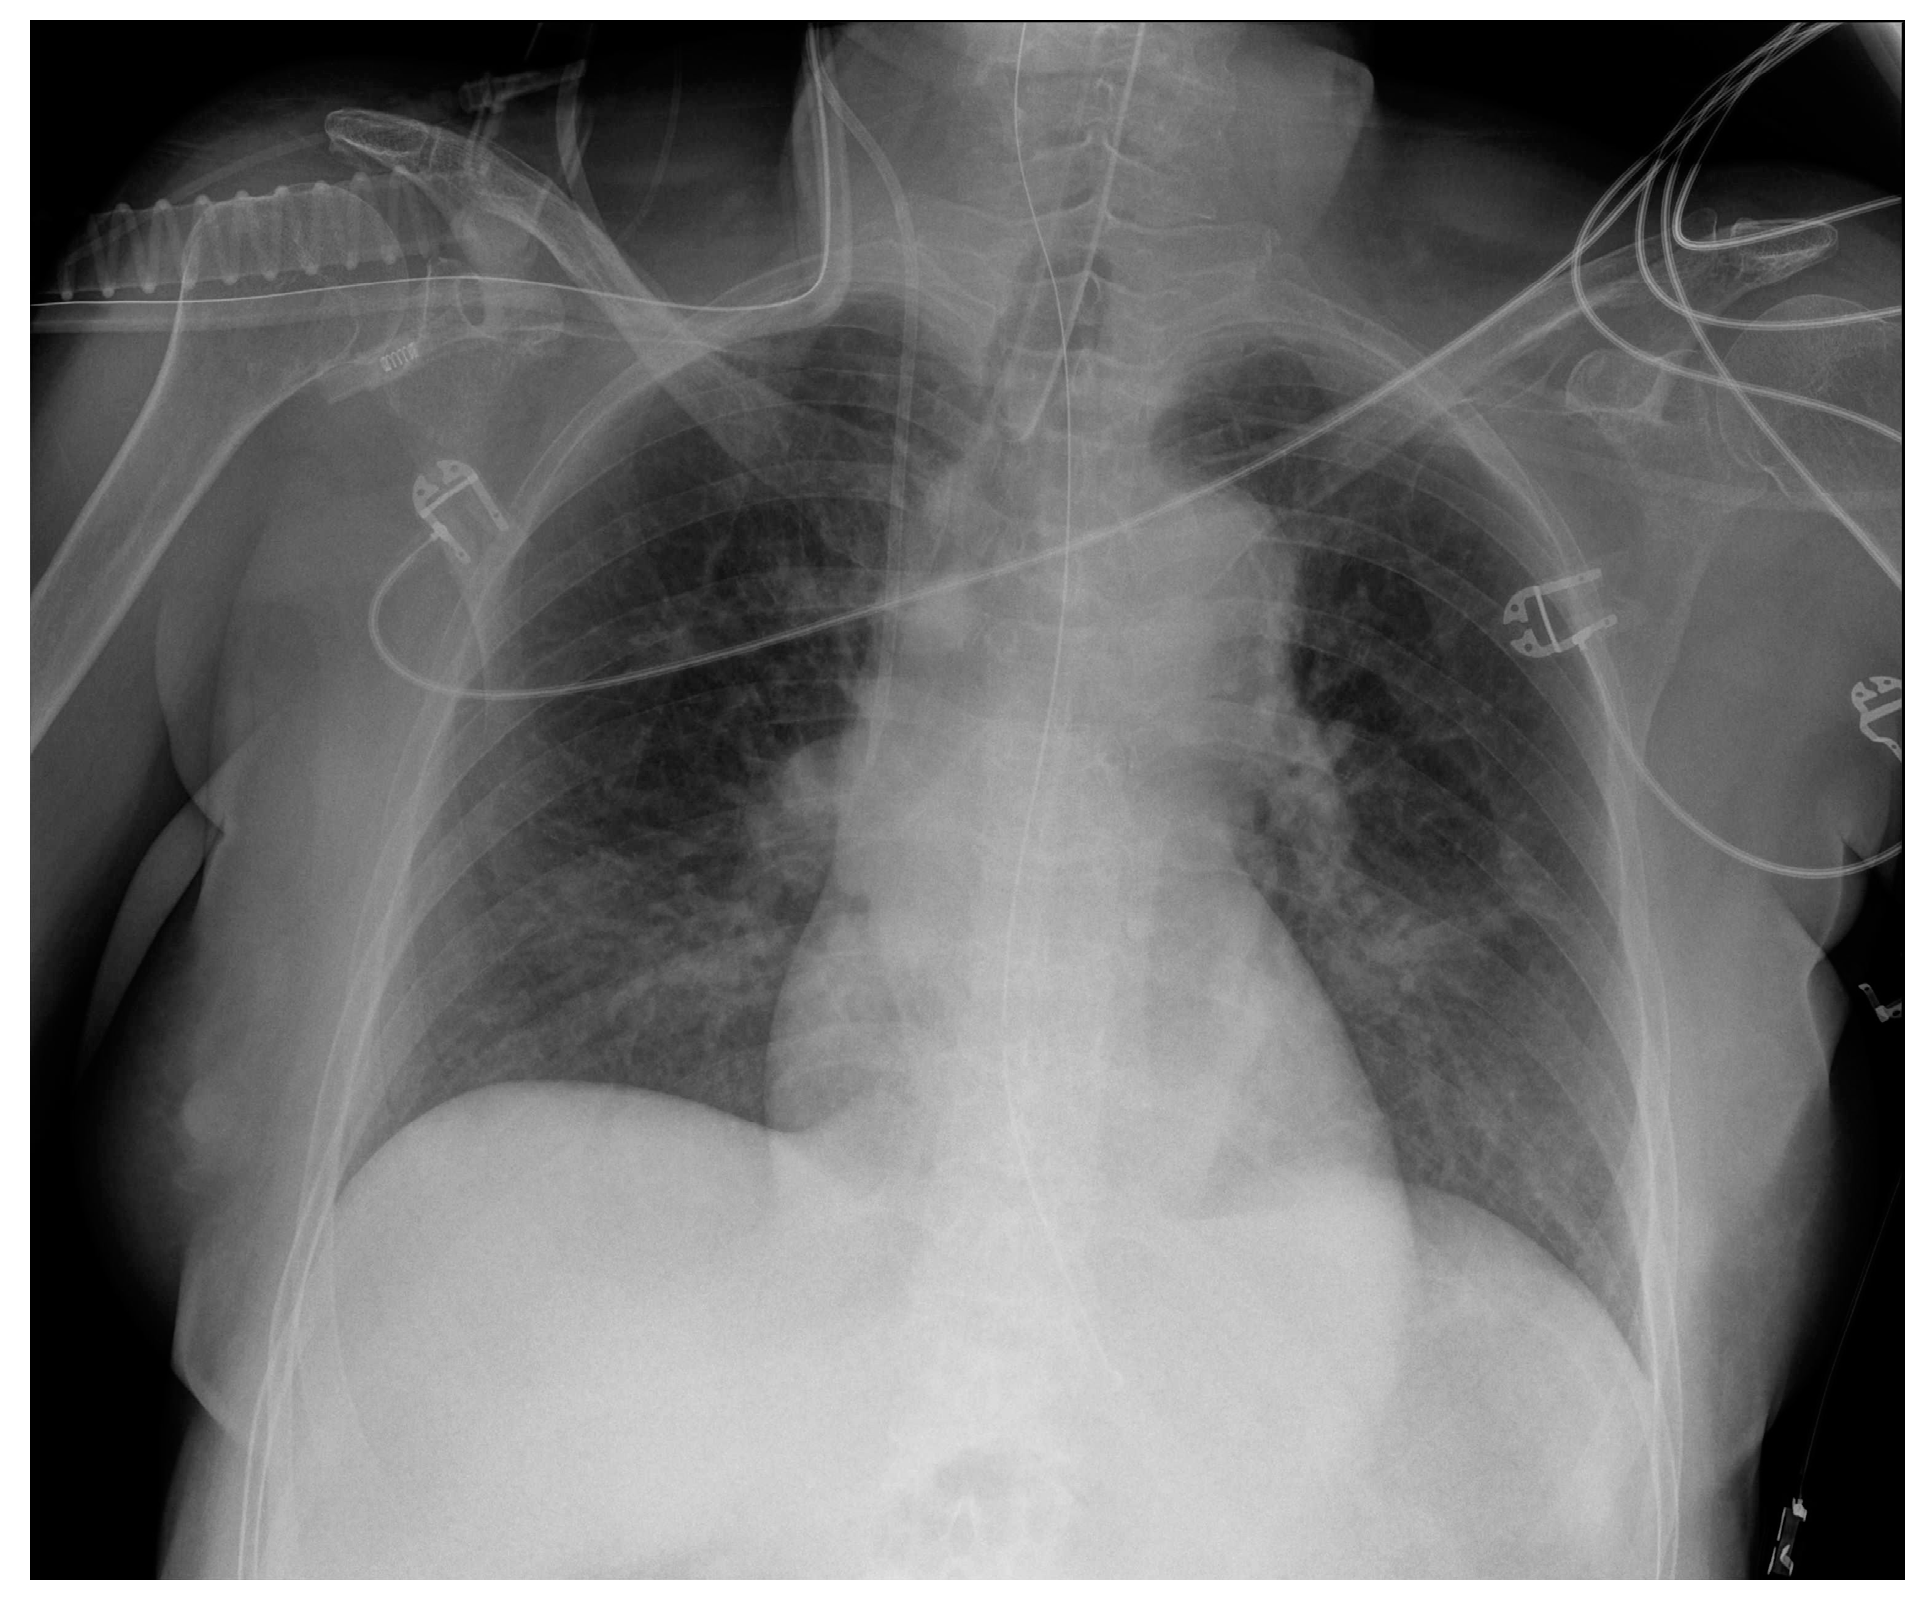

Images of a right pleural effusion before (a) and after (b) drainage through an inferior-posterior chest tube. Right enlargement of the upper mediastinum is also present.